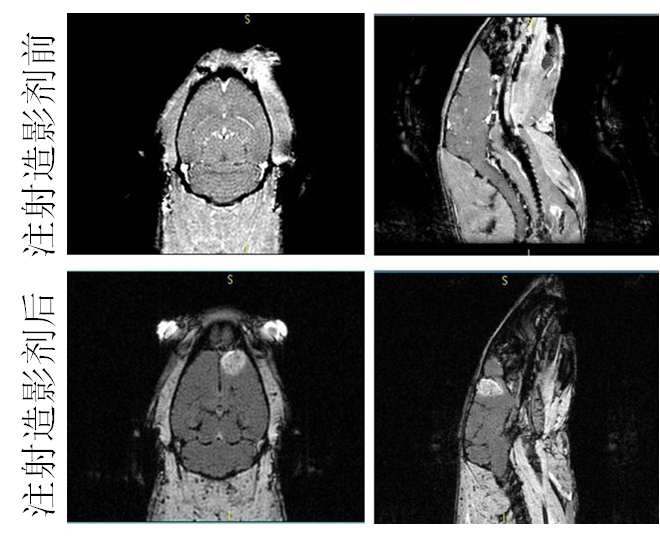

´ÅÐÔÄÉÃײÄÁÏ×÷Ϊ´Å¹²Õñ£¨MRI£©ÔìÓ°¼ÁµÄÓ¦ÓÃ